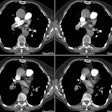

PURPOSE: To evaluate the feasibility and safety of endovascular stent-graft

placement in treating Stanford type B aortic dissection. MATERIALS AND METHODS:

Seven patients underwent endovascular stent-graft placement for type B aortic

dissection. Five patients had acute and two had chronic dissection. In five

patients, the proximal entry tear was within 2 cm of the origin of the left

subclavian artery, and in two patients it was beyond this site. In three

patients, the noncovered proximal portion of the stent-graft was placed across

the origin of the left subclavian artery. The efficacy of the procedure was

assessed at follow-up studies 3, 6, 12, and 24 months after intervention.

RESULTS: The procedure was technically and clinically successful in six patients

(86%). The left subclavian artery remained patent in all patients. In two

patients with involvement of aortic branches, endovascular stent-graft placement

restored adequate blood flow to the compromised branches. One patient was

readmitted 1 month later because the dissection extended into the ascending

aorta. In all but this patient, closure of the entry tear and thrombosis of the

false lumen along the stent-graft were achieved. All false lumina shrank

considerably. The mean follow-up time was 14 months (range, 1-25 months).